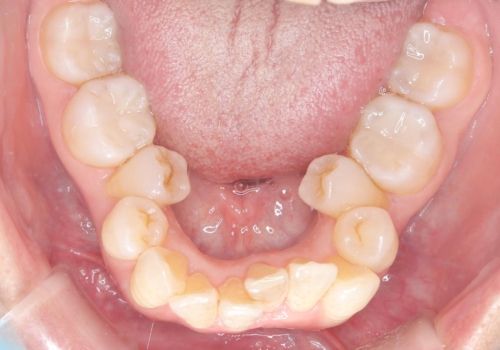

- 主訴:口を開けると所々入っている銀の詰め物が目立つので白い物にやり替えたい。

下顎大臼歯部に入っている保険適用のメタルインレーを、適合性と審美性の良いセラミックインレーでのやり替えとなりました。

メタルインレーを除去した際、古い裏層材やカリエスは除去し新たにCR裏層しています。

セラミックインレーセット時はラバーダム防湿を行っています。